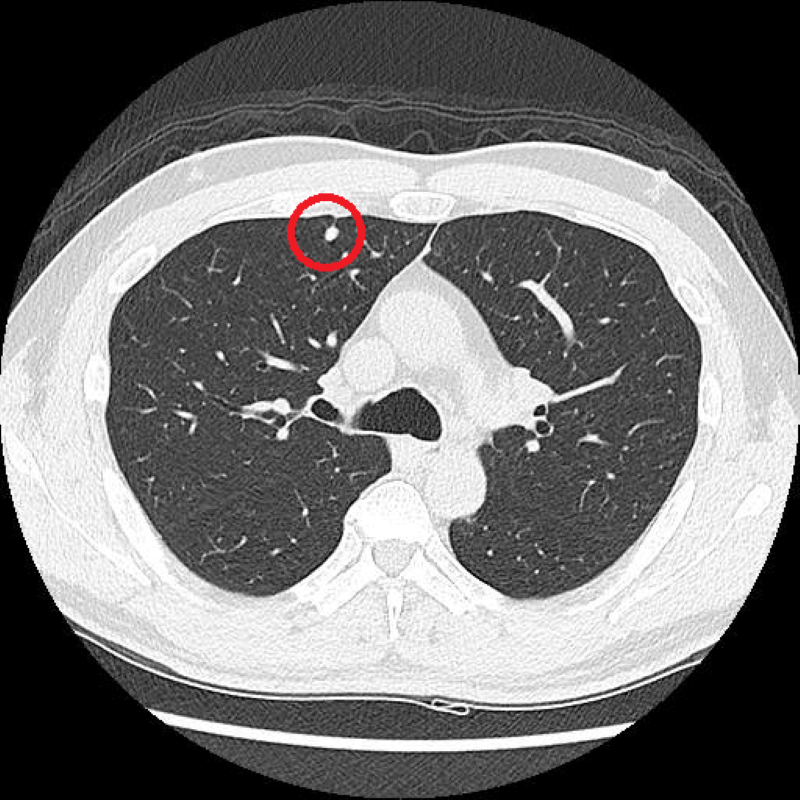

LDCT影像顯示,黃先生的右上肺處有約0.5公分的結節,因無高度惡性特徵,僅需定期追蹤。(台北慈濟醫院提供)

以61歲黃先生為例,戒菸一段時間的他主動接受LDCT篩檢後,發現右上肺有一顆約0.5公分的肺部結節,考量影像沒有高度惡性特徵,陳東仁安排他持續追蹤觀察,若有變大趨勢再進一步討論醫療方針。